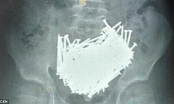

Mắc hội chứng dị thực: Cậu bé nuốt 200 cái đinh vào bụng trong một tháng

Bệnh nhân đau đến mức không thể đi nổi và hoàn toàn mất cảm giác thèm ăn. Bác sĩ liền tiến hành kiểm tra toàn diện, kể cả chụp CT, và hoàn toàn bị sốc với hình ảnh có được. Có đến hai búi tóc và một vết thương lớn trong bụng cô gái.